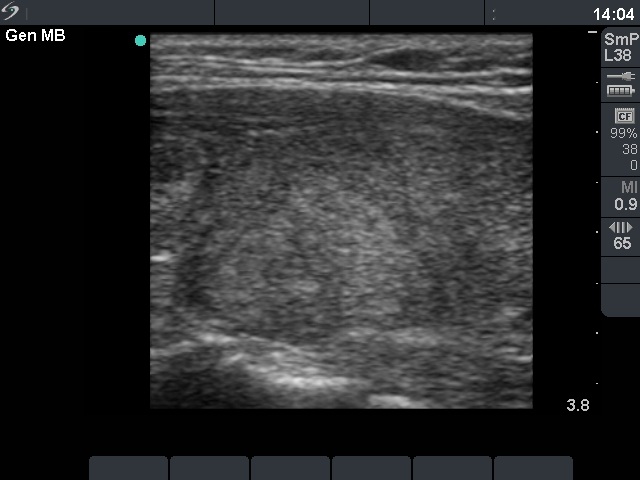

Ultrasonography: a moderately hypoechogenic thyroid was found with multiple circumscribed lesions divided by fibrous tissue. One of these areas contained hyperechogenic granules and exhibited increased vascularization.

The US pattern of this patient highly resembles that of the so-called micronodular form of Hashimoto's thyroiditis. The "nodules" in this case are in truth pseudolobules of the lobes. The prominent appearance of the fibrous tissue dividing the lobules resembles a capsule of a follicular adenoma. In contrast with the latter, not only one or two, but numerous circumscribed areas are present in this case.